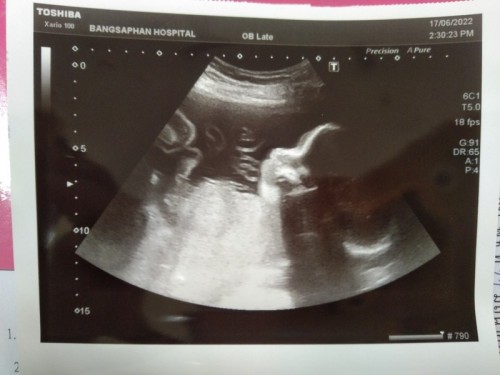

26สัปดาห์4วัน ขนาดลูก930กรัมถือว่าปกติไหมคะ (น้องแอบแซวว่าหัวโตคุณแม่ใจเสียเลยคะ)แต่หมอว่าปกติทุกอย่าง😅😂

แม่สังเกตตอนซาวด์ค่ะ หมอวัดแต่ละส่วนจะมีบอกขนาดว่าอายุประมาณเท่าไหร่ ถ้าสัมพันธ์กับอายุครรภ์ก็หายห่วง ถ้าน้ำหนักน้อยหมอก็จะบอกเองค่ะ ถ้าหมอไม่ว่าอะไรก็ไม่ต้องกังวล

ปกติค่ะ บ้านนี้26w5d 1086 เกินเกณฑ์ ต้องใด้ตรวจเบาหวานอีกทีเดือนหน้าค่ะ

เรา27วีค หนัก900กรัม น้องน้ำหนักตามเกณฑ์ค่ะ

ของเรา26สัปดาห์970หมอบอกตามเกณฑ์นะคะ